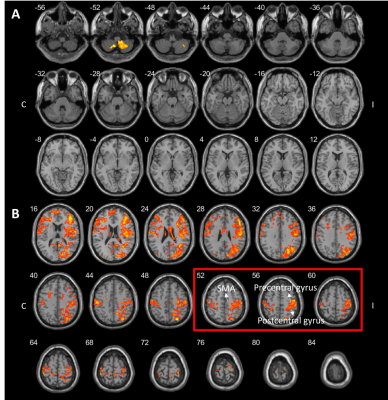

《基于功能连接性预测颅内动脉血栓取出术后缺血性中风的长期运动功能》

Prediction of Long-term Motor Function Based on Functional Connectivity in Ischemic Stroke after Intra-arterial Thrombectomy

该研究背景为急性缺血性中风的标准临床治疗,目的是探讨功能连接性(FC)是否能预测颅内动脉血栓取出术后的长期运动功能恢复。研究对18名急性缺血性中风患者进行了大型血管闭塞治疗,使用Fugl-Meyer Assessment (FMA) 评估运动功能,并在治疗后的不同时间点评估功能网络的变化。基于两周的功能连接性,可以预测患者的长期运动功能,为临床提供适当的康复计划。研究表明,通过评估中风后的功能连接性,可以预测患者的长期运动恢复情况,这对于康复计划的制定具有重要意义。

acad788af0a75069aae7ca1e1a969889.png

图1A. 对于两周和三个月时的小脑网络的配对t检验结果。

图1B. 对于两周和三个月时的感觉运动网络的配对t检验结果。C 健侧(病灶对侧),I 患侧(病灶同侧)。